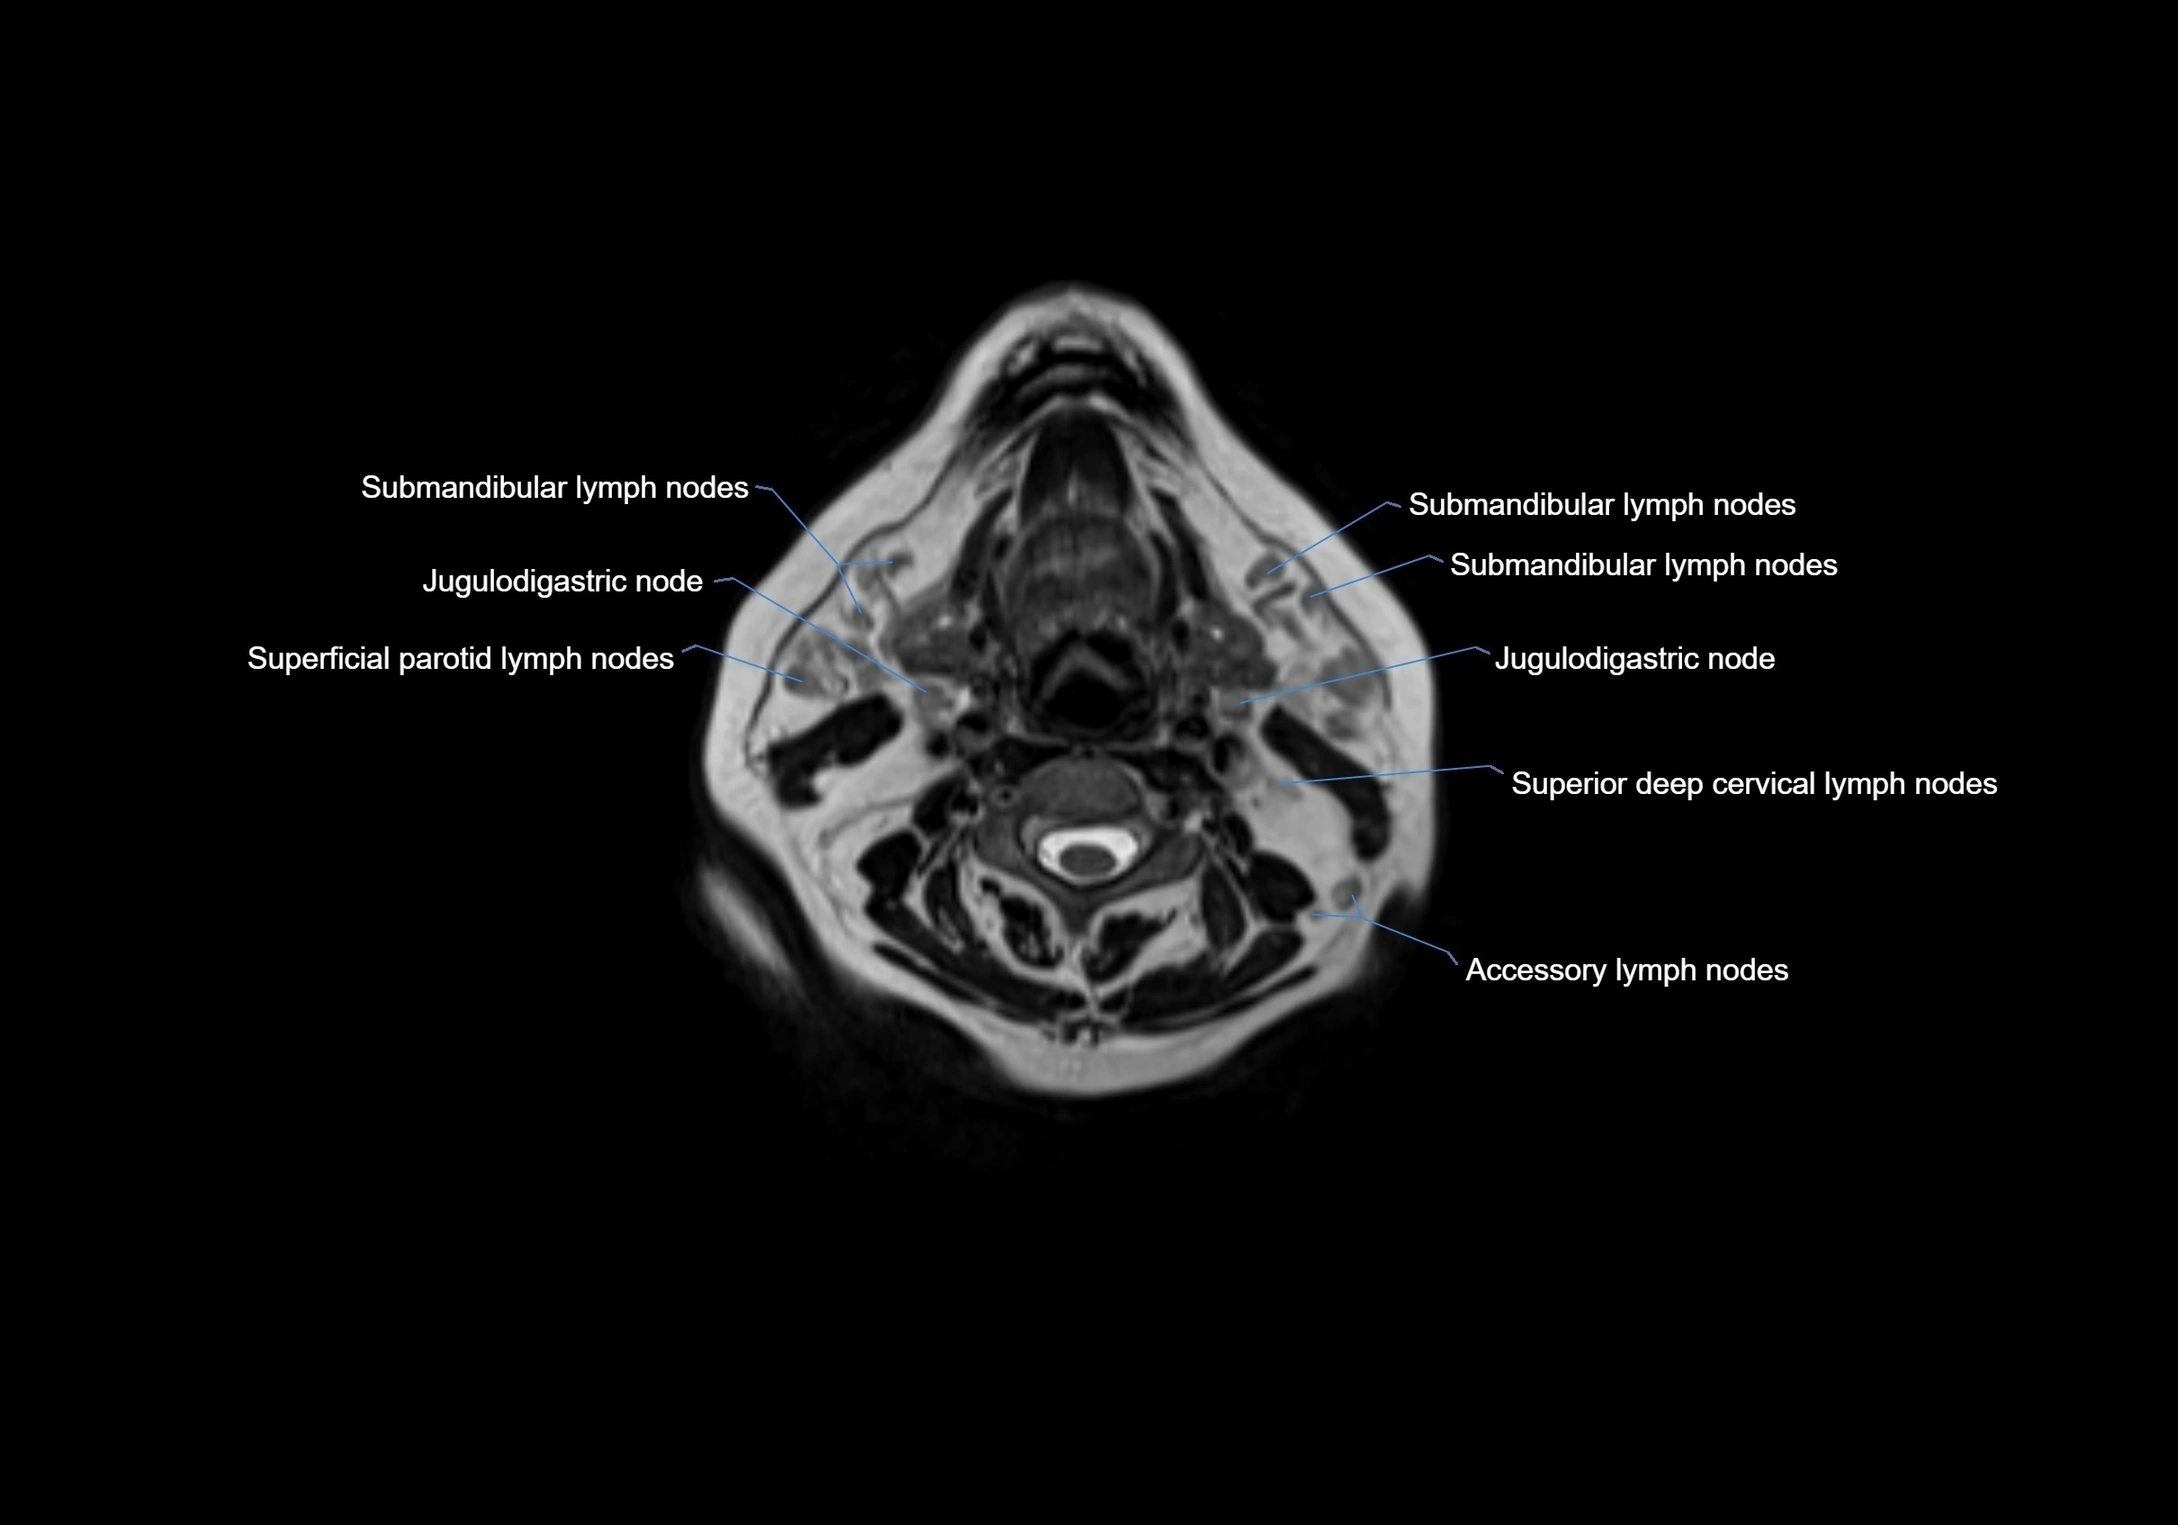

Location

• Found along primary lymph node chains, including preauricular, submandibular, parotid, and occipital regions

• Embedded in subcutaneous fat or superficial fascia, often lateral or posterior to primary nodes

MRI Appearance

T1-weighted images:

• Normal accessory nodes appear as small, oval hypointense to intermediate signal structures within subcutaneous fat

• Surrounded by hyperintense fat, enhancing contrast for visualization

• Pathological nodes may appear enlarged or rounded, sometimes with cortical thickening

T2-weighted images:

• Nodes show intermediate signal, with surrounding fat bright

• Useful for detecting edema, inflammation, or infiltration

• Fatty hilum may appear slightly hyperintense relative to cortex

MRI images

image